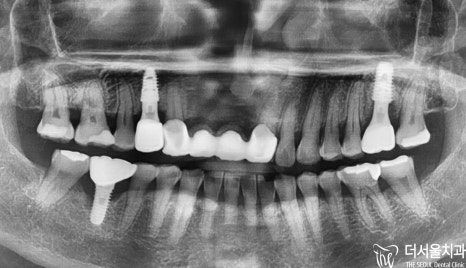

파노라마와 육안으로 보여지듯

보철 수술은 무사히 잘 끝났습니다.

치아 흔들림이 없어지게 되자,

환자분께서 정말 좋아하셨으며

딸이 추천을 해줘서 너무 고맙다며,